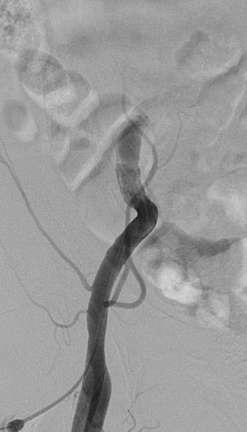

导管操作导致髂外动脉出血